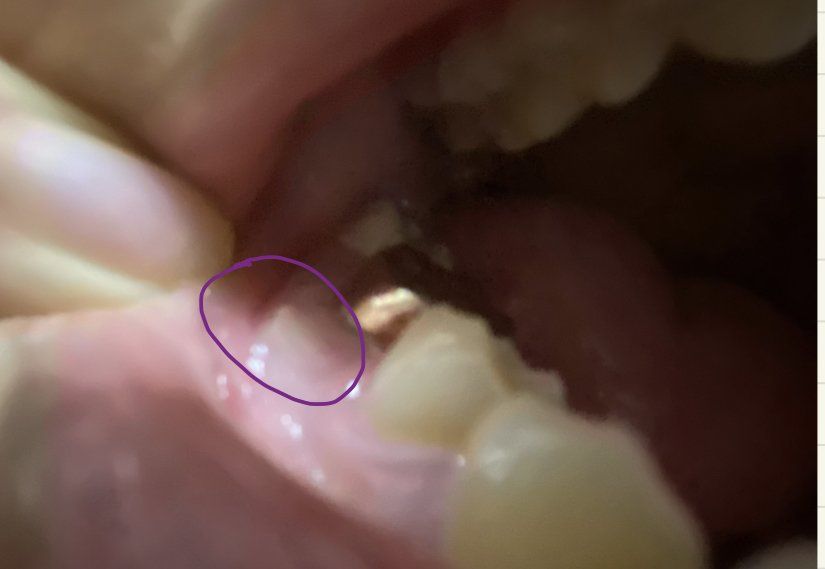

제가 요번 2월달에 치근단절제술을 받았습니다. 받은 후 아무런 통증도 없고 잘 있는 것 같았습니다. 하지만 저번주 토요일부터 잇몸 옆에 흰색 고름이 생기기 시작했습니다. 이게 염증인 것 같은데 염증만 빼고 지켜보면 될까요? 임플란트는 사정상 안 될 것 같습니다. 보라색 동그라미 안에가 흰색 고름이 생긴 부분 입니다.

• 1번 째 사진